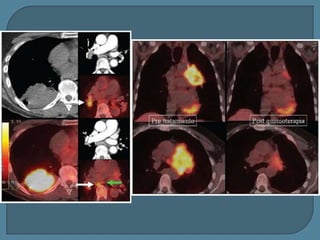

Tiempo de duplicación de 60 días, sugestivo de malignidad. La TC muestra un nódulo

lobulado que se biopsió: adenocarcinoma